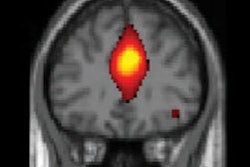

New findings are coming out on almost a weekly basis about trace elements of gadolinium left in human tissue after scans with MRI contrast agents. What do we know about this phenomenon, and how serious is it? We talk to Dr. Robert McDonald, PhD, of the Mayo Clinic in Rochester, MN.